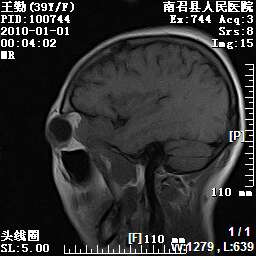

以下是引用随光逐影在2010-1-22 9:03:00的发言:[br]考虑左侧中颅窝(蝶骨翼区)脑膜瘤侵犯蝶骨翼并突入左侧眼眶。

以下是引用水过无痕在2010-1-22 14:55:00的发言:[br]一、定位:颅外占位;二、定性:恶性可能性大;三、组织来源:来源于左侧眼外直肌或其他部位;考虑为:横纹肌肉瘤>转移瘤>脑膜瘤.